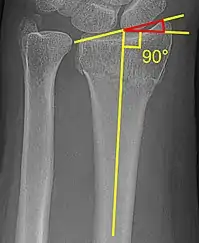

The radial inclination of a distal radius fracture is shown in red in image at right. The angle is measured between:[4][5]

- A line drawn between the distal ends of the articular surface of the radius on an AP view of the wrist.

- A line that is perpendicular to the diaphysis of the radius.

Radial inclination is normally 21-25°.[6]